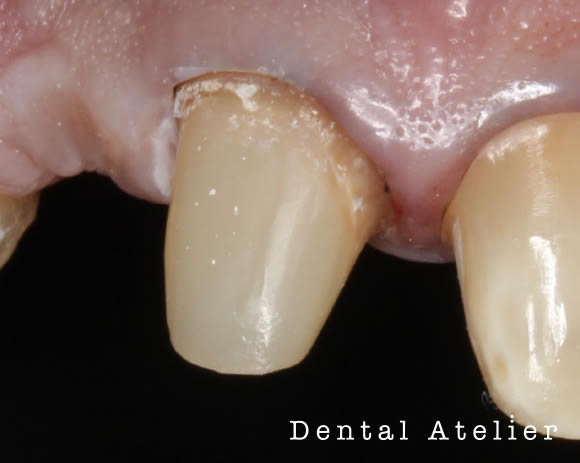

支台築造(土台・コア)ファイバーコア・ファイバーポストについて

ファイバーコア(ポスト)とは、根の治療(根管治療)をした歯に必要な、歯を補強する治療です。

神経を取った歯は、補綴治療「かぶせ物(クラウン)」をしなくてはいけません。その際に残っている歯に、土台(コア)を建てることを支台築造と言います。

神経を取った歯

支台築造された歯

土台が出来上がった歯には写真のように作られた「かぶせ物(クラウン)」が入りますので、かぶせ物をセットして治療が終了します。

その土台の内部にグラスファイバー繊維(ファイバーコア・ポスト)を使うことで、歯を補強し、破折(歯が割れない・折れない)ようにするのがファイバーを使った支台築造です。

当院で行う支台築造はラバーダムを使用し細菌感染をなくし、歯に精密に埋めることで歯とファイバーが一体化し、歯への負担を減らすことが可能となります。

精度の高い支台築造を提供できます。

作られたセラミック歯

かぶせたセラミック歯